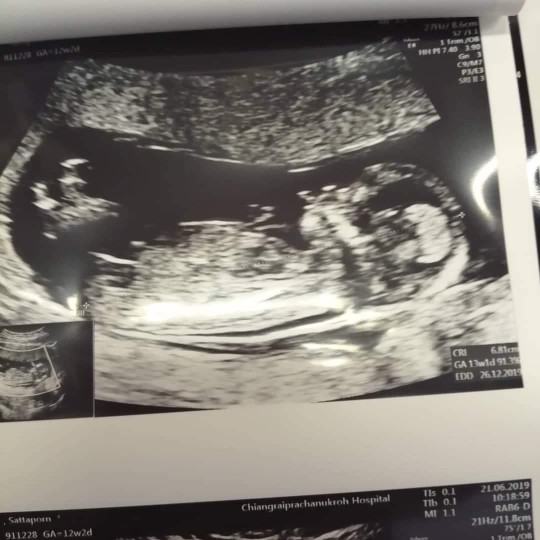

12 weeks ค่ะ

11+3จ้า

ตอนนี้15+2แล้วจ้า กำหนดคลอดประมาน25ธันวา จ้า